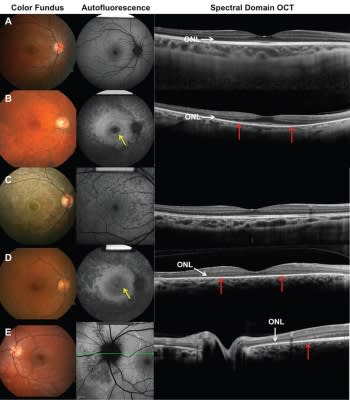

Figure 2. Color fundus, autofluorescence (AF), and SD-OCT. A) Normal control. B) Autosomal-dominant retinitis pigmentosa. Fundus shows vessel attenuation and waxy pallor disc. A ring of hyperautofluorescence (yellow arrow) is visible on AF. OCT shows loss of the ellipsoid line (red arrows) and thinning of the outer nuclear layer. C) Congenital rubella. Fundus image shows the characteristic “salt and pepper” pattern at the RPE level, with no intraretinal pigmentary migration. Speckled appearance of hyper- and hypoautofluorescence is visible on AF. OCT findings are normal. D) Autoimmune retinopathy. Fundus findings show vessel attenuation with no intraretinal pigmentary migration. AF and OCT show findings undistinguishable from RP. E) AZOOR. Fundus findings show pigmentary disturbance around the optic disc. The typical zone of hypo- and hyperautofluorescence can be seen on AF. OCT reveals peripapillary losses of the ellipsoid line, outer nuclear layer, and RPE.

While detailed history taking and systematic review are very helpful in differentiating these conditions, multiple imaging modalities (Figure 2) and diagnostic tests are often also required (Table).